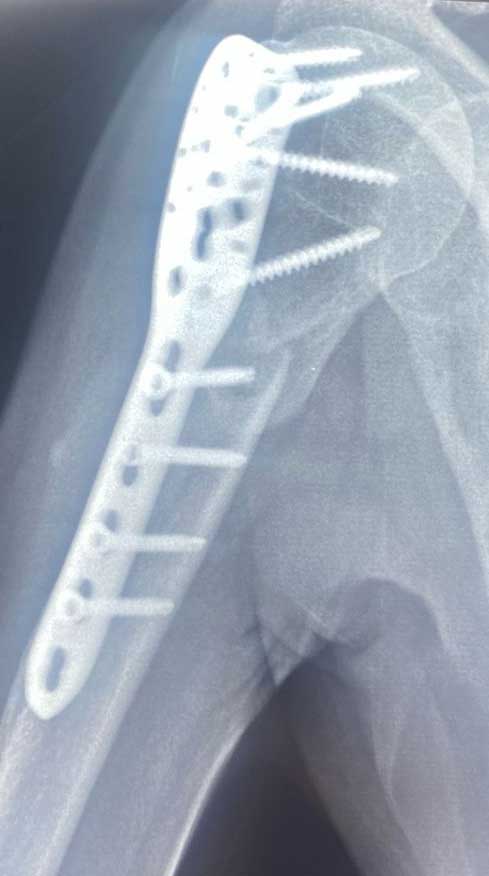

Pérdida de la continuidad del tejido óseo de la articulación del hombro, articulación acromioclavicular o cintura escapular, las cuales están constituidas por humero, escápula y clavícula.

El tratamiento puede ser quirúrgico o conservador (no quirúrgico) el cual estará determinado por las características del paciente, el hueso fracturado y el desplazamiento de los fragmentos, el cual puede consistir en inmobilizaciones o cirugías abiertas, mínima invasivas ó artroscopicas.

Es necesario cuidar la osteosíntesis del hombro por semanas después de la cirugía, apegado a la terapia física frecuente para evitar el dolor del edema y rigidez postquirúrgica. Los protocolos para la rehabilitación del hombro quirúrgico están muy bien protocolizados y estandarizados para mejorar el resultado y varían de 4-12 semanas.

En cuanto a fracturas de hombro es decir del humero proximal, escápula o articulación glenohumeral es importante siempre tener en cuenta el grado de la lesión, es decir, la complejidad del numero de estructuras óseas y si afecta o no la articulación, y si es una fractura con múltiples fragmentos. Pero la intención de una cirugía es siempre conseguir el mejor resultado funcional para mejorar la calidad de vida del paciente.